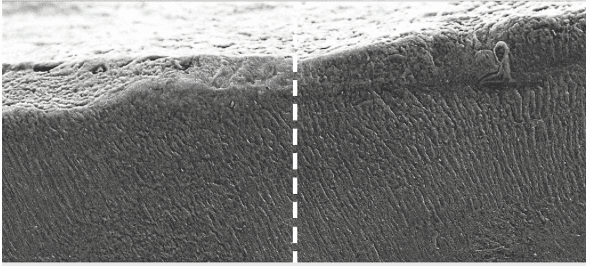

Keratin, tükürükteki kalsiyum ve fosfat mineralleriyle etkileşime girerek diş yüzeyinde mine benzeri kristal bir tabaka oluşturuyor. Bu tabaka, hem diş minesini güçlendiriyor hem de hassasiyeti azaltıyor. Araştırmaya göre, bu yöntem erken aşamadaki çürükleri durdurma potansiyeline sahip.